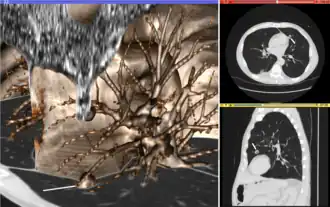

Visualization

Visualization plays several key roles in medical image computing. Methods from scientific visualization are used to understand and communicate about medical images, which are inherently spatial-temporal. Data visualization and data analysis are used on unstructured data forms, for example when evaluating statistical measures derived during algorithmic processing. Direct interaction with data, a key feature of the visualization process, is used to perform visual queries about data, annotate images, guide segmentation and registration processes, and control the visual representation of data (by controlling lighting rendering properties and viewing parameters). Visualization is used both for initial exploration and for conveying intermediate and final results of analyses.

The figure "Visualization of Medical Imaging" illustrates several types of visualization: 1. the display of cross-sections as gray scale images; 2. reformatted views of gray scale images (the sagittal view in this example has a different orientation than the original direction of the image acquisition; and 3. A 3D volume rendering of the same data. The nodular lesion is clearly visible in the different presentations and has been annotated with a white line.